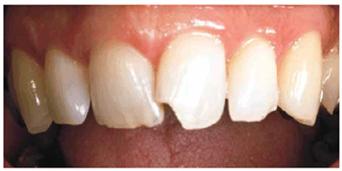

harmonious in size. Figures 24-6A 24-6B, and 24-6C provide an example of how one tooth

can be crowned to relieve anterior crowding. After the adjacent central and

lateral incisors were reshaped, a full porcelain crown was placed on the left

central (see Figure 24-6B

Figure 24-6A: This patient presented with chipped and crowded maxillary anterior teeth.

Figure 24-6B: A full porcelain crown was placed on the left central incisor; the right central and lateral incisors were esthetically contoured.

Figure 24-6C: The post-treatment radiograph shows the change in axial inclination for esthetic result.